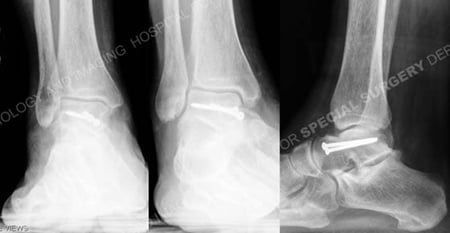

Anteroposterior, mortice and lateral radiographs at 1 year illustrating a healed talus fracture.